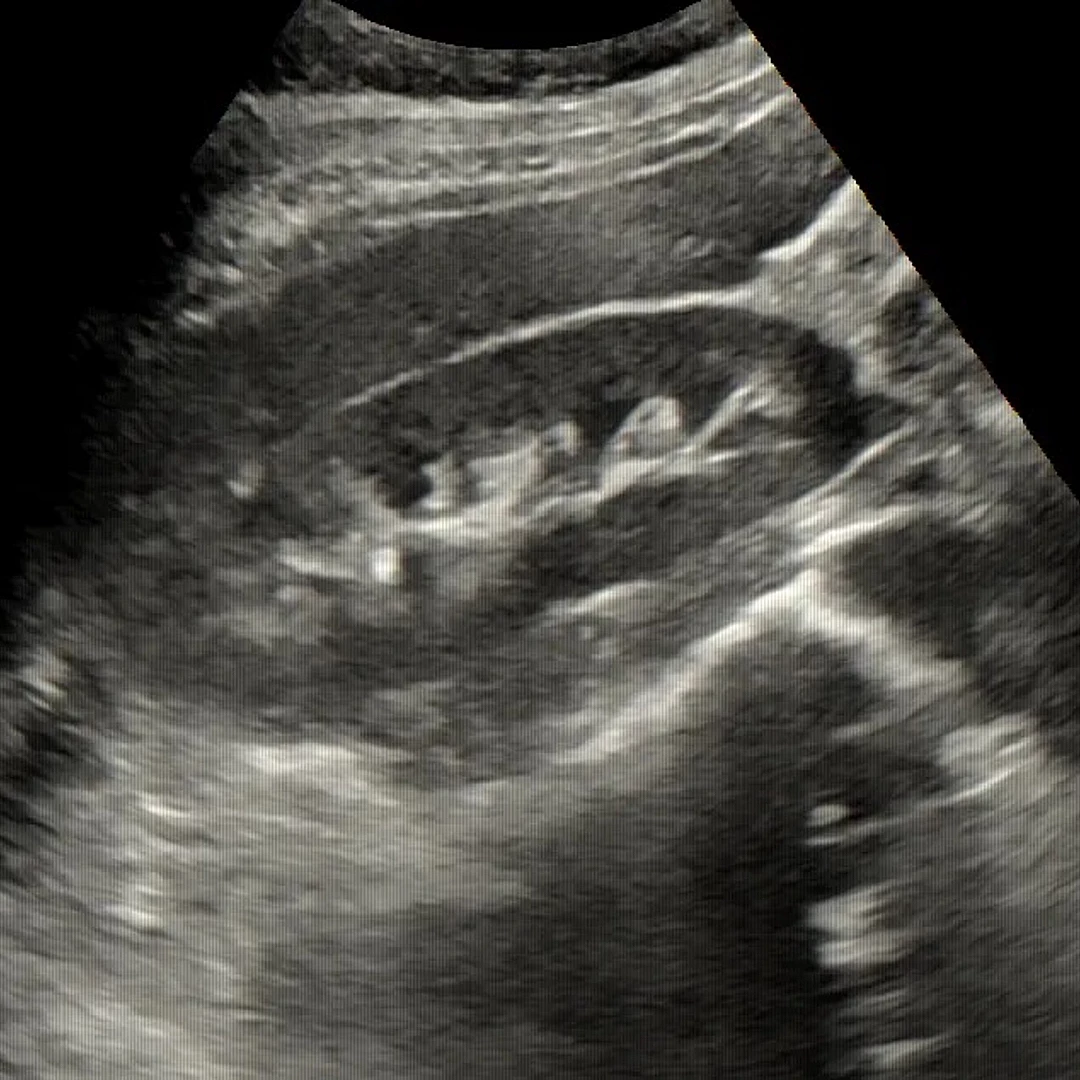

Abdominal Ultrasound

Abdominal Ultrasound uses sound waves to visualize organs like the liver, kidneys, gallbladder, and pancreas. It’s a non-invasive, radiation-free scan ideal for diagnosing pain, swelling, or abnormalities in the abdomen.